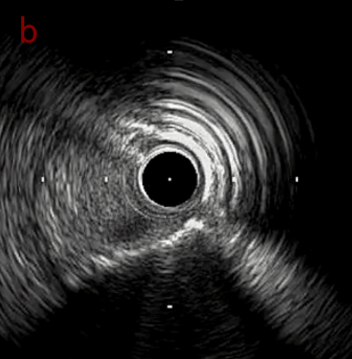

IVUS after OAS low speed 3回

IVUS imaging after low speed 3回

OAS low speedによる引きのsandingを3回行いIVUSを確認するとa-cでは心筋側側へのOASによる良好なbias変化と、それに伴いdの健常側への危険なbias変化を認めた。

そのためcでIVUSマーキングを行い、その点より引きで赤線のpinpoint OAS high speedを行い、dに関してはinjury回避のためにOASを当てない方針とした。